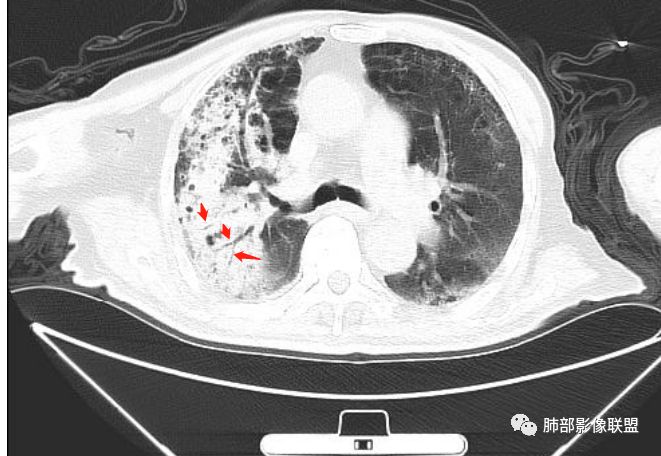

老年男性,咳嗽气喘10天,双肺明显肺气肿,右上肺叶实变,内见大量空洞及囊腔样改变(部分为支气管扩张),实变区周围表现为网格样改变,有明显的小叶间隔增厚,边界似清非清,支气管走行僵硬,有枯树枝样改变,双下肺胸膜下小叶间隔增厚明显,边缘相对模糊,综合考虑如下:1、粘液腺癌可能大(枯树枝样改变,边界似清非清,小叶间隔增厚符合)。2、结核,右上肺似像干酷样改变,内有空洞及支扩样改变支持,但下肺及左肺无相关支气管播散的小叶中心结节及树芽,不支持,临床病症不支持,只有咳嗽,喘气,无咳痰及结核中毒症状。当然结核是妖,需要结合痰检及结核相关指标进一步明确。3、肺克,虽有10年糖尿病史,但肺部只有右肺改变明显,无胸膜下脓肿表现,无脓毒栓表现,临床症状也不支持。4、其他感染?双下肺胸膜下病灶边缘模糊,不完全除外,需要结合临床炎性指标分析。

右上肺大片状高密度影,呈蜂窝样改变,部分气腔无壁,部分呈厚壁改变,内部结构紊乱,部分边缘GGO边界清楚,大小不一,病灶近端小远端大,近端支气管壁增厚,支持感染性病变,考虑结核,其内支气管呈枯树枝改变,病灶局部膨隆,内部结构紊乱,边界的GGO部分清楚,恶性(腺癌)待排。

老年男性,糖尿病患者。右肺病变,病灶区多发树芽、管状透亮区,考虑为扩张支气管,说明为支气管源性病变。结核?真菌?肺癌?病灶区多发空洞,空洞内坏死不太彻底,树芽征跟增殖结节不明显,结核先不考虑。病灶区晕征不太明显,边界相对清楚,小叶间隔增厚~似呈结节状改变,支气管枯树枝征。最后,肺癌首先考虑,粘液腺癌?鉴别曲霉菌

2、支气管:干酪样肺炎内的支气管破坏的,扩张的,粘液腺癌小支气管多狭窄的堵塞的,大支气管较完好,枯枝征。

6、结核灶周围磨玻璃少见,粘液腺癌磨玻璃影清楚。结核灶常有收缩,钙化,树丫等等。很重要,粘液腺癌分布弥漫,远处飘散的边界清楚的磨玻璃结节影有重要诊断意义。